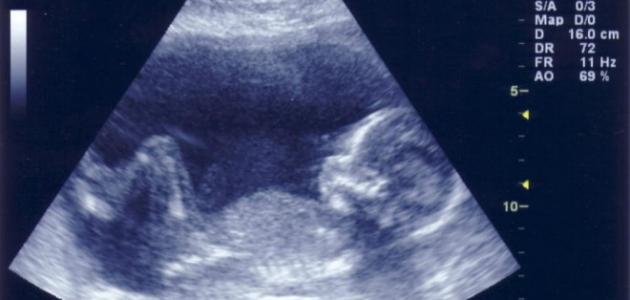

لا شك أنّ المرأة الحامل تكون على شوق لمعرفة جنس مولودها، ولا تنتظر حتى يأتي الشهر الرابع لتفحص جنس الجنين باستخدام جهاز التلفزيون الطبي، ولكن قد تريد بعض النساء معرفة جنس المولود في الشهر الأول من الحمل، وهو ما لا يمكن معرفته باستخدام التلفزيون، لذا قمنا بوضع بعض الطرق التي كانت تستخدم قديماً لتخمين نوع الجنين، مع العلم أنّ هذه طرق غير علمية ولا تعطي نتائج حقيقية، ويبقى العلم عند الله.